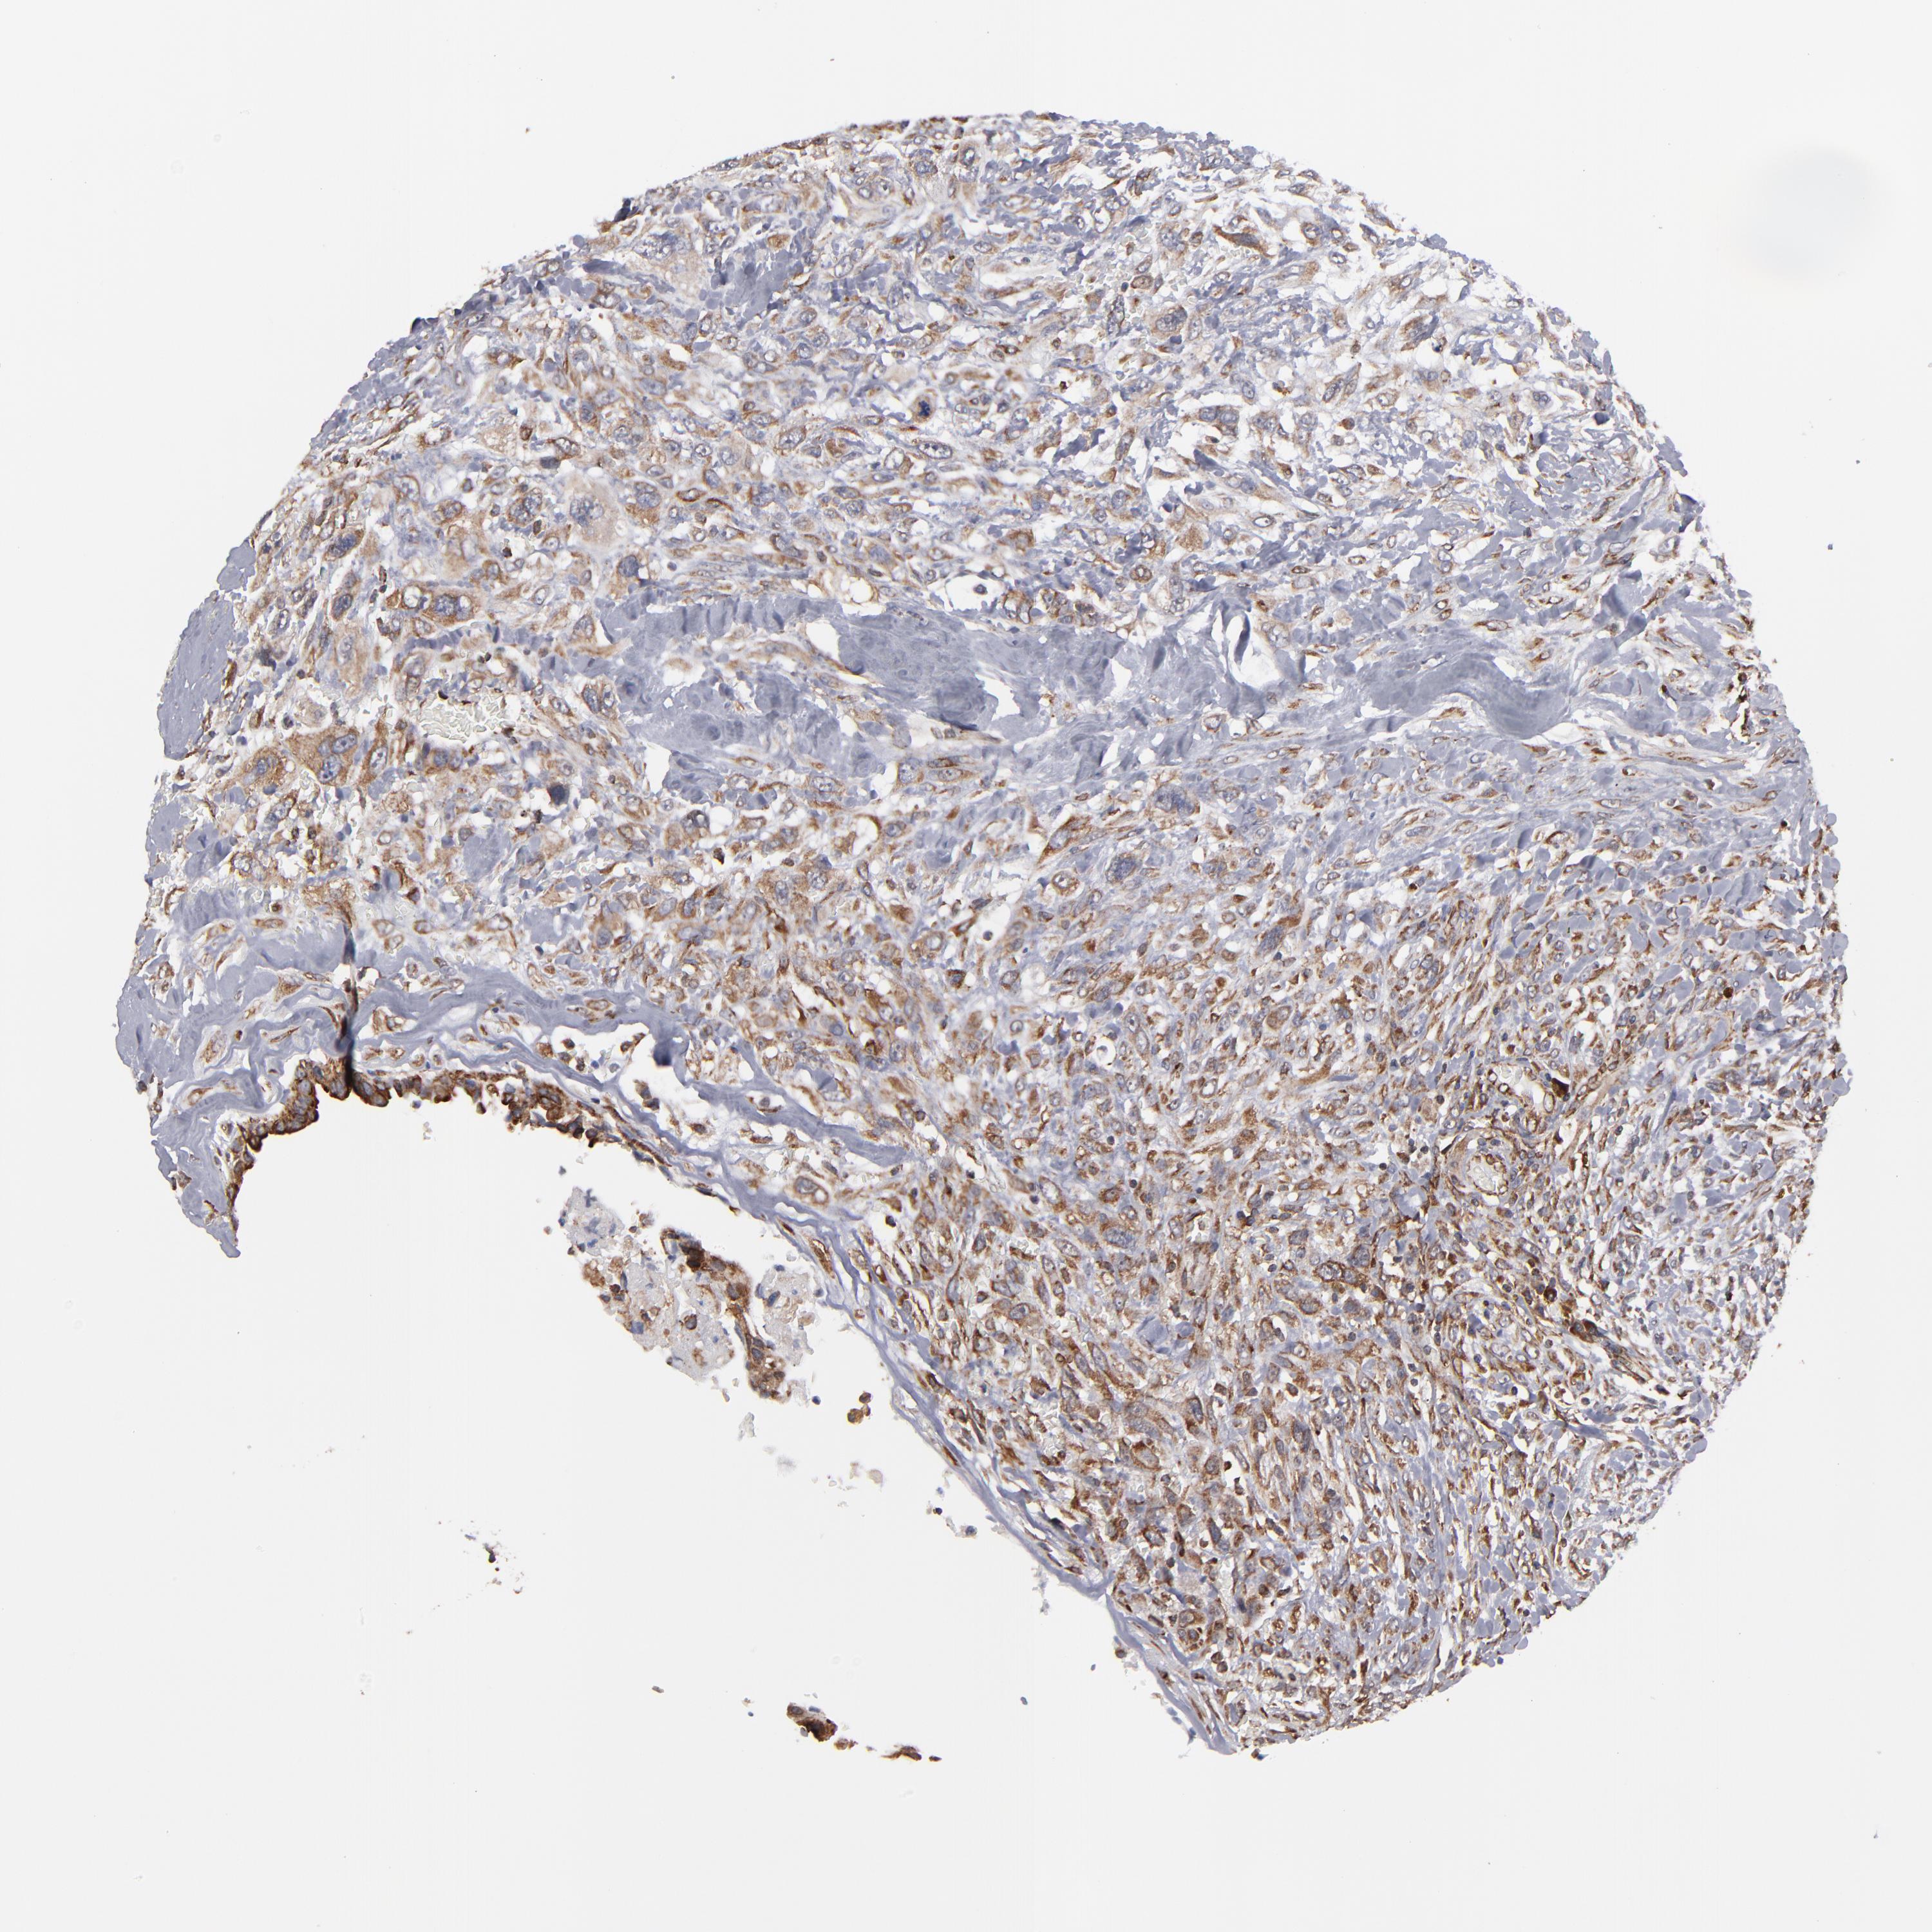

CANCER BREAST CANCER Show tissue menu

BRCA TCGA BRCA VALIDATION PROTEIN EXPRESSION